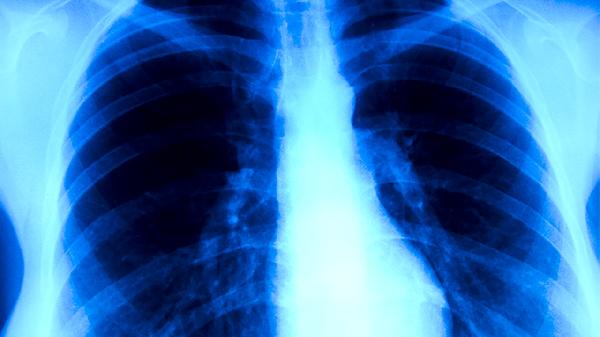

30岁小伙查出肺结核,医生紧急提醒:忽视这个症状可能埋下肺癌隐患!

30岁的小王最近总感觉胸口发闷,偶尔咳嗽几声也没当回事。直到某天加班时突然咳出血丝,才慌忙去医院检查,结果CT报告单上“肺结核”三个字让他瞬间懵了。更让他后怕的是医生那句:“再拖下去,肺组织反复损伤可能诱发更严重的问题......”

1、定期做肺部影像检查

治愈后头三年每半年要做一次低剂量CT,之后每年一次。有吸烟史或家族史者需要更密切监测。

普通胸片可能漏诊早期微小病变,低剂量CT能发现毫米级的结节变化。